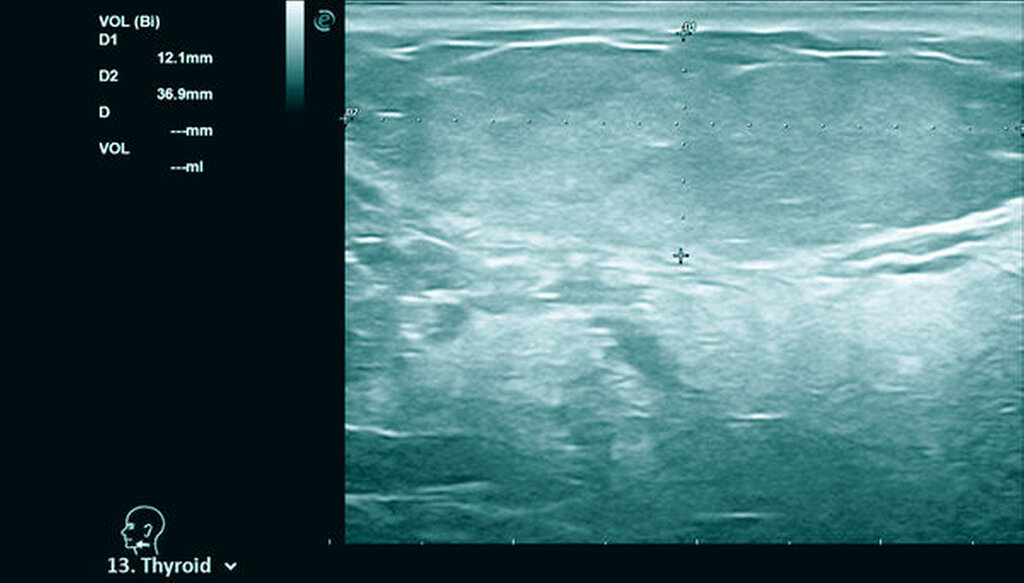

Palpatorisch präsentierte sich ein prall-kugeliger Tumor, der zum umliegenden Gewebe gut verschieblich war. Die bildgebende Diagnostik mittels B-Mode-Sonografie zeigte eine echoreiche, scharf begrenzte Raumforderung mit dorsaler Schallverstärkung (Abbildung 2). Aus der Zusammenschau aus klinischem und sonografischem Bild wurde der Verdacht auf ein Lipom gestellt. Die alio loco angefertigte MRT bekräftigte diese Verdachtsdiagnose, zudem zeigte sich darin die Unterbrechung des Platysma durch das verdrängende Wachstum des Befunds in die Tiefe (Abbildung 3).